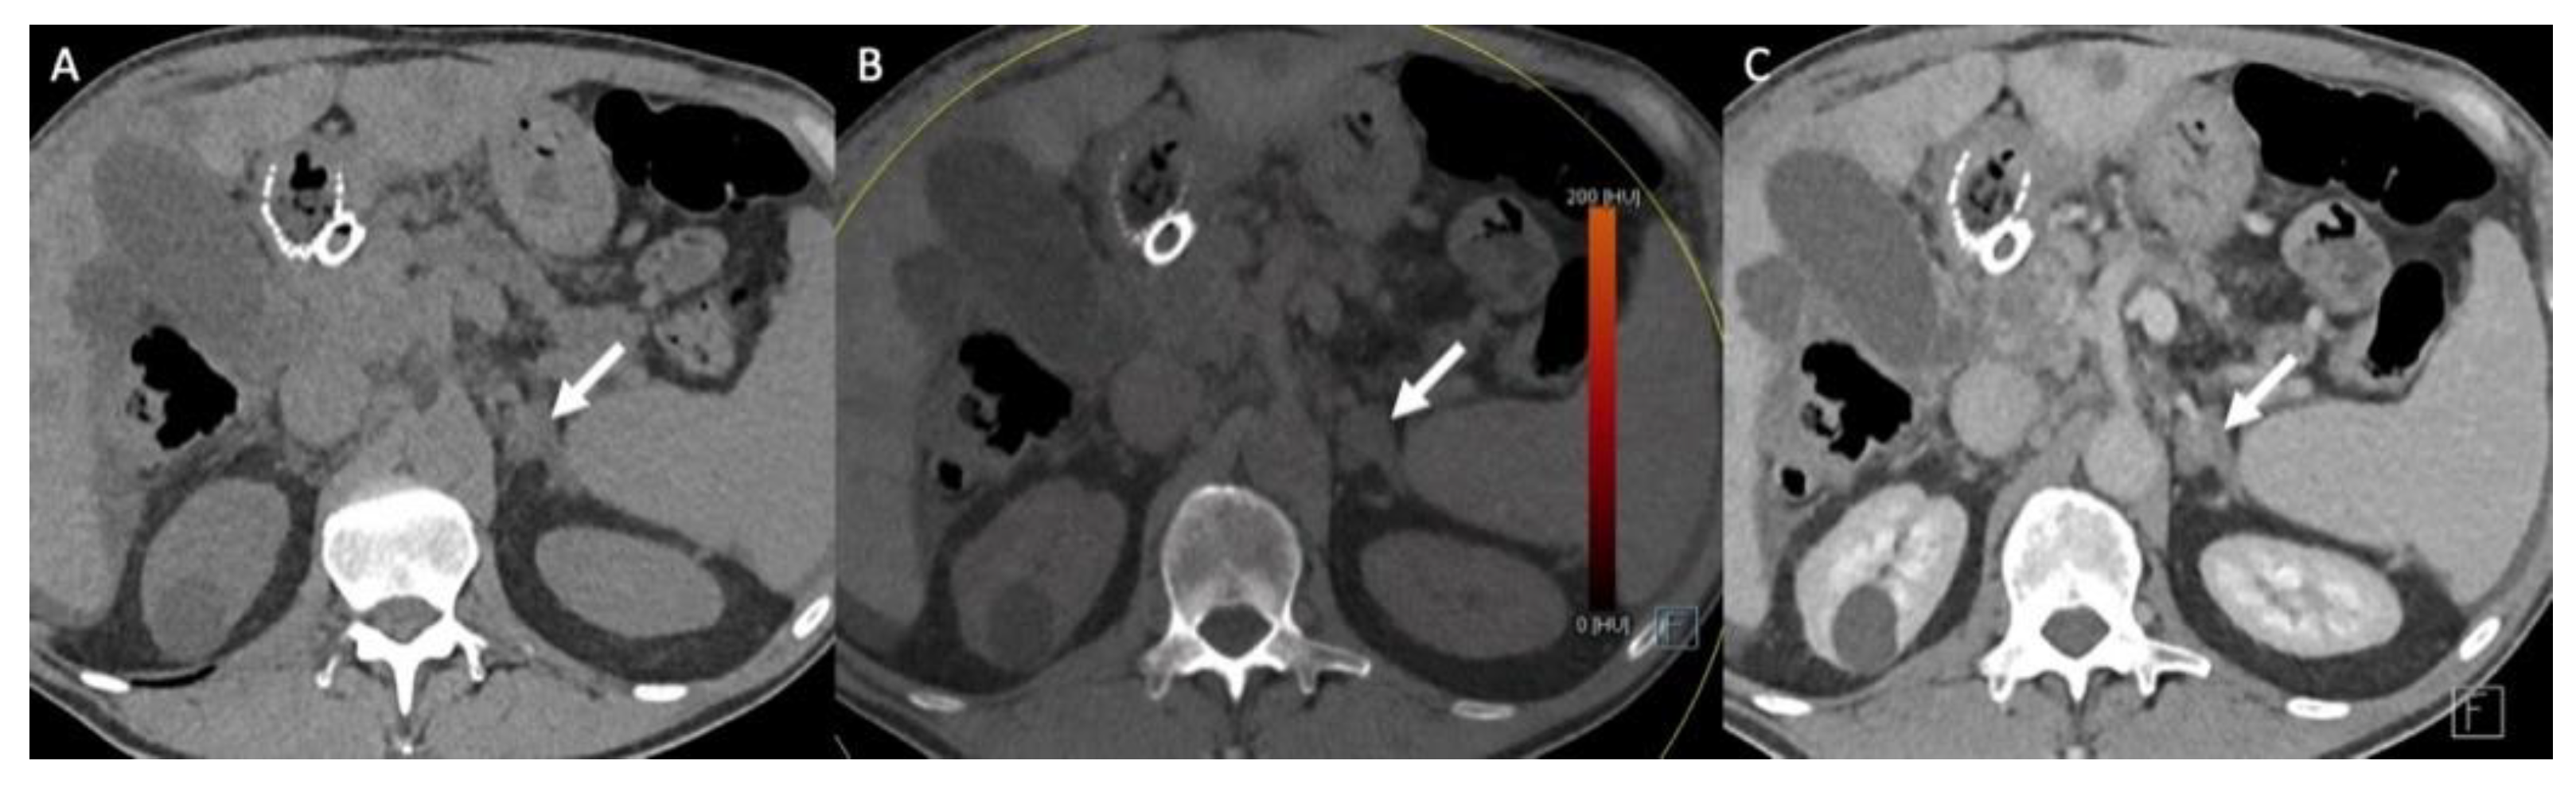

- Hindman, N.M.; Megibow, A.J. One-Stop Shopping: Dual-Energy CT for the Confident Diagnosis of Adrenal Adenomas. Radiology 2020, 296, 333–334. [Google Scholar] [CrossRef]

- Jamali, S.; Michoux, N.; Coche, E.; Dragean, C.A. Virtual unenhanced phase with spectral dual-energy CT: Is it an alternative to conventional true unenhanced phase for abdominal tissues? Diagn. Interv. Imaging 2019, 100, 503–511. [Google Scholar] [CrossRef]

- Nagayama, Y.; Inoue, T.; Oda, S.; Tanoue, S.; Nakaura, T.; Ikeda, O.; Yamashita, Y. Adrenal Adenomas versus Metastases: Diagnostic Performance of Dual-Energy Spectral CT Virtual Noncontrast Imaging and Iodine Maps. Radiology 2020, 296, 324–332. [Google Scholar] [CrossRef]

- Lestra, T.; Mule, S.; Millet, I.; Carsin-Vu, A.; Taourel, P.; Hoeffel, C. Applications of dual energy computed tomography in abdominal imaging. Diagn. Interv. Imaging 2016, 97, 593–603. [Google Scholar] [CrossRef]

- Connolly, M.J.; McInnes, M.D.F.; El-Khodary, M.; McGrath, T.A.; Schieda, N. Diagnostic accuracy of virtual non-contrast enhanced dual-energy CT for diagnosis of adrenal adenoma: A systematic review and meta-analysis. Eur. Radiol. 2017, 27, 4324–4335. [Google Scholar] [CrossRef] [PubMed]